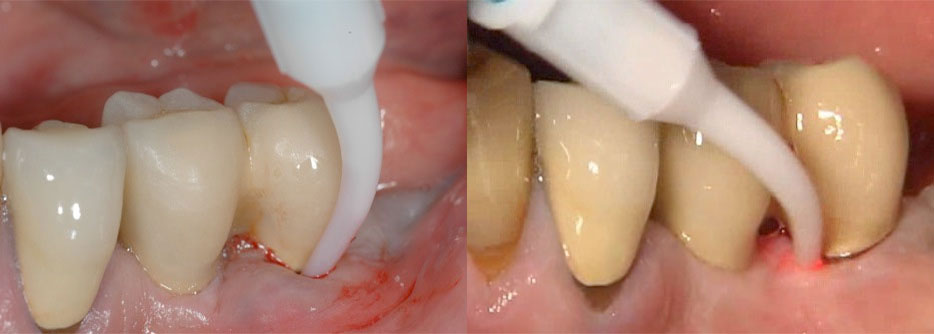

In evaluating the bony structures adjacent to the implants over long periods of time, conventional radiography is a widely applied technique in clinical practice. However, it should be noted that minor changes in bone morphology in the crestal area may not be revealed until they reach a significant size and shape. Nevertheless, DIB (the Distance from the Implant shoulder to the alveolar Bone crest) represents a reliable radiographic parameter for long term monitoring in clinical practice provided that optimal exposure geometry has been achieved. Usually, the apical termination of the cylindrical part of implant fixtures is used as a reference point in two stage systems, despite the fact that subcrestal placement utilizing a countersink procedure is recommended for most submerged implant systems.

Digital Subtraction Radiography (DSR) and CBCT

The use of computer assisted image analysis such as subtraction radiography may improve the diagnostic accuracy (sensitivity) of radiographs as it allows detection of small changes in bone density In digitizing radiographs of identical exposure geometry, minute changes in the level and density of the alveolar bone may be revealed by subtracting subsequent images from a baseline radiograph. For clinical research, DSR is highly recommended and has been successfully applied in longitudinal studies. Multi-slice computer tomography and cone beam volume imaging have been used in implant dentistry offering the advantage that osseous structures can be represented in three planes, true to scale and without overlay or distortion.